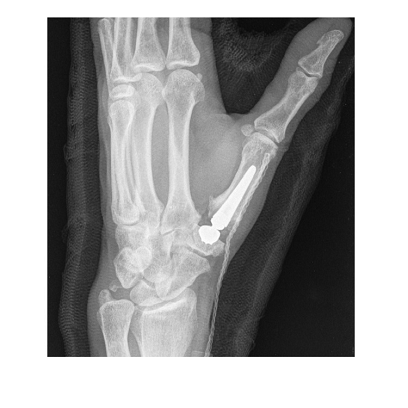

Stosowane implanty – Touch CMC I

W naszym ośrodku wykorzystujemy implanty Touch CMC I, które charakteryzują się:

- dwumobilną konstrukcją, umożliwiającą ruch w dwóch miejscach,

- bardzo dobrą ruchomością stawu,

- wysoką stabilnością, co wiąże się z niskim ryzykiem zwichnięcia.

Dzięki temu pacjenci zyskują większy komfort po zabiegu, a rehabilitacja przebiega szybciej i skuteczniej.